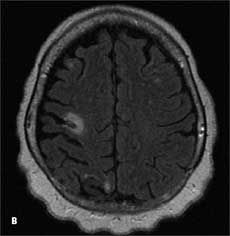

A previous transthoracic echocardiogram with a bubble study did not reveal any cardiac source of embolism. Axial MRI of the brain on admission showed an abnormal signal in the bilateral hemispheres representative of multiple subacute infarcts (Aand B); the right posterior frontal and right posterior parietal cortical and subcortical regions appeared to be most affected. A transesophageal echocardiogram revealed a severely thick atherosclerotic plaque with a large pedunculated mobile complex atheroma (C, arrow) in the upper descending aorta; the aortic arch showed severe atherosclerotic plaques with maximal thickness up to 10 mm (D).